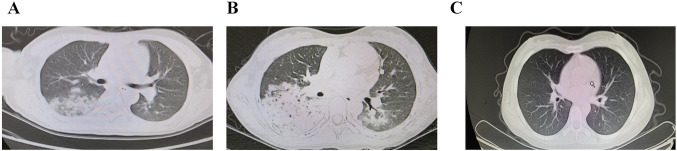

Secondary vasculitis is encountered in about one-third of all cases of systemic lupus erythematosus (SLE). Skin is most commonly involved in lupus-related small vasculitis. Although antineutrophil cytoplasmic autoantibodies (ANCA) associated vasculitis (AAV) is relatively uncommon, it can be the most dangerous manifestation associated with high mortality. SLE and AAV are separate diseases with different pathophysiologies and an overlap syndrome has only been reported a few times in previous literature. We present a unique case of a pediatric patient of pulmonary-renal syndrome, presenting with pulmonary alveolar hemorrhage and rapidly progressive glomerulonephritis. Serological and biopsy findings were suggestive of SLE and AAV occurring, simultaneously. Renal biopsy demonstrated necrotizing and crescentic glomerulonephritis, superimposed on diffuse segmental proliferative lupus glomerulonephritis class IV. The presentations of autoimmune diseases and vasculitis can be multi-systemic. Considering overlap syndromes, especially in patients with underlying connective tissue disease or systemic vasculitis, is vital for prompt therapy and prevention of morbidity in this population.